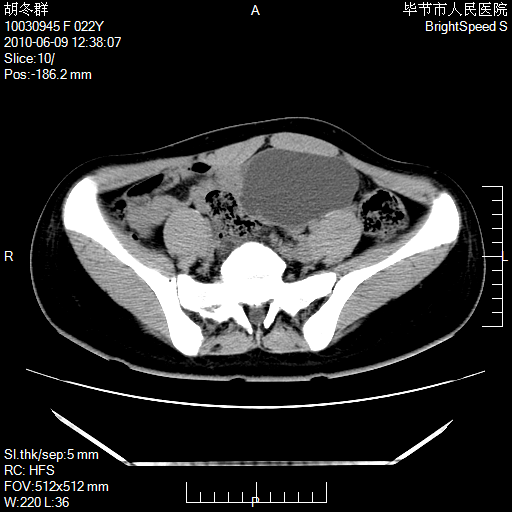

患者23岁,发现腹部包块3月。

左侧卵巢囊腺瘤或囊腺癌

盆腔内囊性占位性病变;考虑左侧卵巢囊腺瘤。

有分隔、壁薄,支持考虑左侧卵巢囊腺瘤。

左侧卵巢浆液性囊腺瘤。

支持考虑左侧卵巢囊腺瘤;宫腔积液。

有分隔、壁薄,支持考虑左侧卵巢囊腺瘤。排尿后,膀胱缩小,由于重力作用,肿块下移就到了膀胱位置,很好理解。